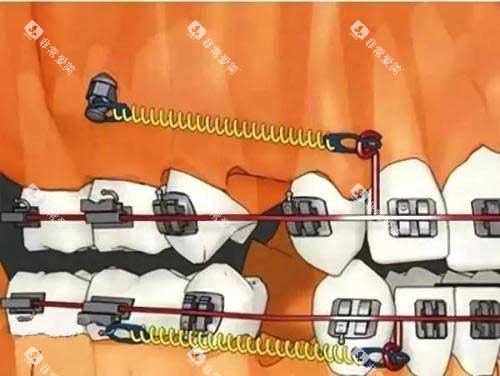

(一)传统金属托槽矫正

价格区间:8000 - 15000 元

项目介绍:价格较为实惠,是经济型矫正方式,但美观度相对较低。

(二)自锁托槽矫正

价格区间:10000 - 20000 元

项目介绍:相比传统托槽,舒适度和矫正效率更高,复诊间隔时间更长。